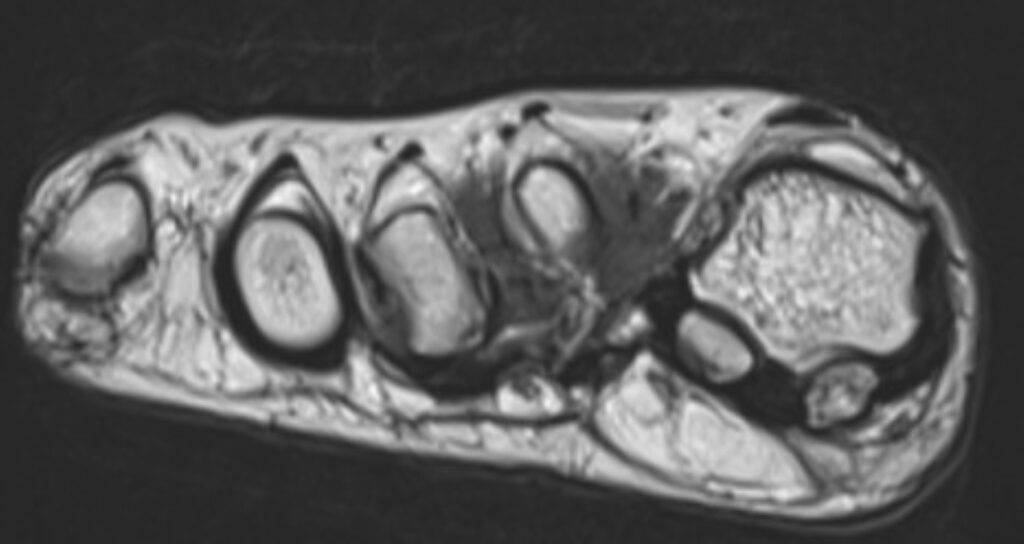

Fuß MRT Bild, verschiedene Perspektiven